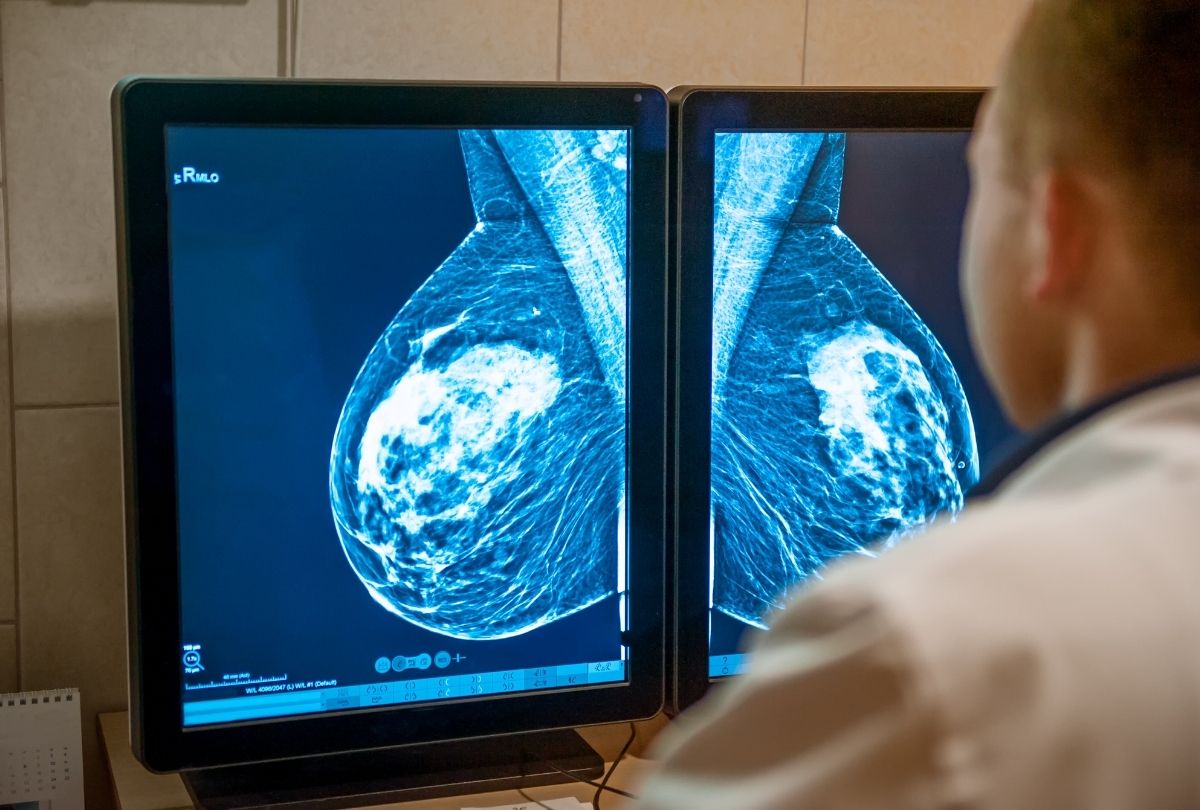

One of the most important advancements is the 3D mammogram, also known as breast tomosynthesis. Unlike traditional mammograms, a 3D mammogram creates a layered, three-dimensional view of the breast, which allows doctors to detect abnormalities that may otherwise be hidden.

3D mammography, or breast tomosynthesis, revolutionized screening by taking multiple X-ray images at different angles. A computer reconstructs these images into a detailed 3D model, allowing radiologists to examine breast tissue slice by slice. This layered approach helps reveal abnormalities that might be hidden in traditional 2D images.

A 3D mammogram is an advanced imaging technique that produces a multi-layered image of the breast. Unlike a standard mammogram that captures a single flat image, a 3D mammogram captures multiple thin slices, giving doctors a detailed view of tissue structures.

During a 3D mammogram, the X-ray arm sweeps over the breast, capturing numerous images from different angles. These images are then compiled into a 3D model on a computer, which allows radiologists to “scroll” through each layer. This method improves visualization of dense tissue and helps detect tumors earlier.